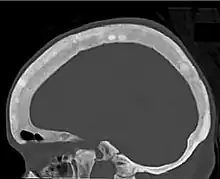

Renal osteodystrophy is usually diagnosed after treatment for end-stage kidney disease begins; however the CKD-MBD starts early in the course of CKD.[1][6] In advanced stages, blood tests will indicate decreased calcium and calcitriol (vitamin D) and increased phosphate, and parathyroid hormone levels. In earlier stages, serum calcium, phosphate levels are normal at the expense of high parathyroid hormone and fibroblast growth factor-23 levels. X-rays will also show bone features of renal osteodystrophy (subperiostic bone resorption, chondrocalcinosis at the knees and pubic symphysis, osteopenia and bone fractures) but may be difficult to differentiate from other conditions. Since the diagnosis of these bone abnormalities cannot be obtained correctly by current clinical, biochemical, and imaging methods (including measurement of bone-mineral density), bone biopsy has been, and still remains, the gold standard analysis for assessing the exact type of renal osteodystrophy.[6][16]